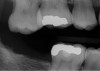

Fig 1. In 2009 patient No. 1 presented with a missing tooth at site No. 31.

Figure 1

Fig 2. In 2016 patient No. 1 manifested no alterations of tooth position No. 2.

Figure 2

Another consideration is mean vertical displacement of unhampered posterior teeth, which in some studies was minimal: 0.8 mm37 and 0.9 mm30 (Table 1). Yet, there could have been sites where the amount of extrusion was clinically relevant. When Lindskog-Stokland et al assessed the risk of over-eruption using 1 mm as a threshold, they stated there was an odds ratio of 3.3 that unimpeded molars would extrude 1 mm compared to opposed molars.30 Based on their calculations, however, it is unclear which patients with a missing molar are at risk of over-eruption (Figure 1 through Figure 4). Indeed, if susceptible individuals could be identified, then restorative therapy could be initiated to stabilize their occlusion (eg, tooth replacement). Furthermore, odds ratios can be highly misleading, and predictive values would provide clinicians a better perspective as to what percentage of sites may experience significant extrusion.41,42